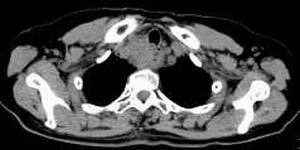

女,61岁,吞咽困难(包括开水)已久。

食道中上段癌并锁骨上窝淋巴结转移.

1、同意食道上段ca併淋巴结转移。

2、做食道呑钡就一目了然。

3、右侧甲状腺是否有问题?是否甲状腺ca转移食道上段。因为肿块顶部图像没有,请楼主展示,谢谢!

食道中上段中分化鳞癌伴锁骨上淋巴结转移

大家都很正确,谢谢!